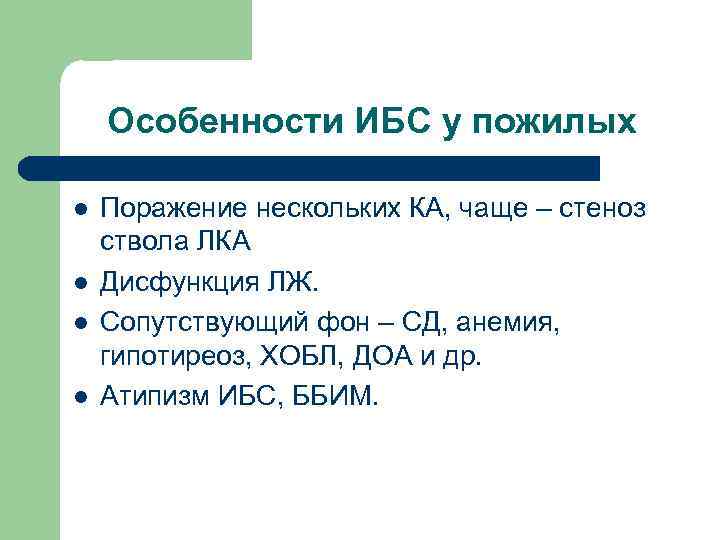

Особенности ИБС у пожилых l l Поражение нескольких КА, чаще – стеноз ствола ЛКА Дисфункция ЛЖ. Сопутствующий фон – СД, анемия, гипотиреоз, ХОБЛ, ДОА и др. Атипизм ИБС, ББИМ.